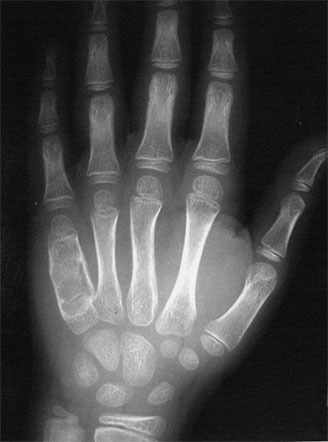

Bone tumors are rare lesions. A large part of these tumors are benign lesions, and they often occur by chance during radiological examinations for another reason. As a complaint, they usually show swelling and pain. Rarely, it is diagnosed after causing a fracture in the place where it was. Osteoid osteoma, osteochondroma (exostosis), enchondroma, non-ossifying fibroma, eosinophilic granuloma, simple bone cyst, fibrous dysplasia and intraosseous lipoma/ganglion are the most common lesions of benign tumors.